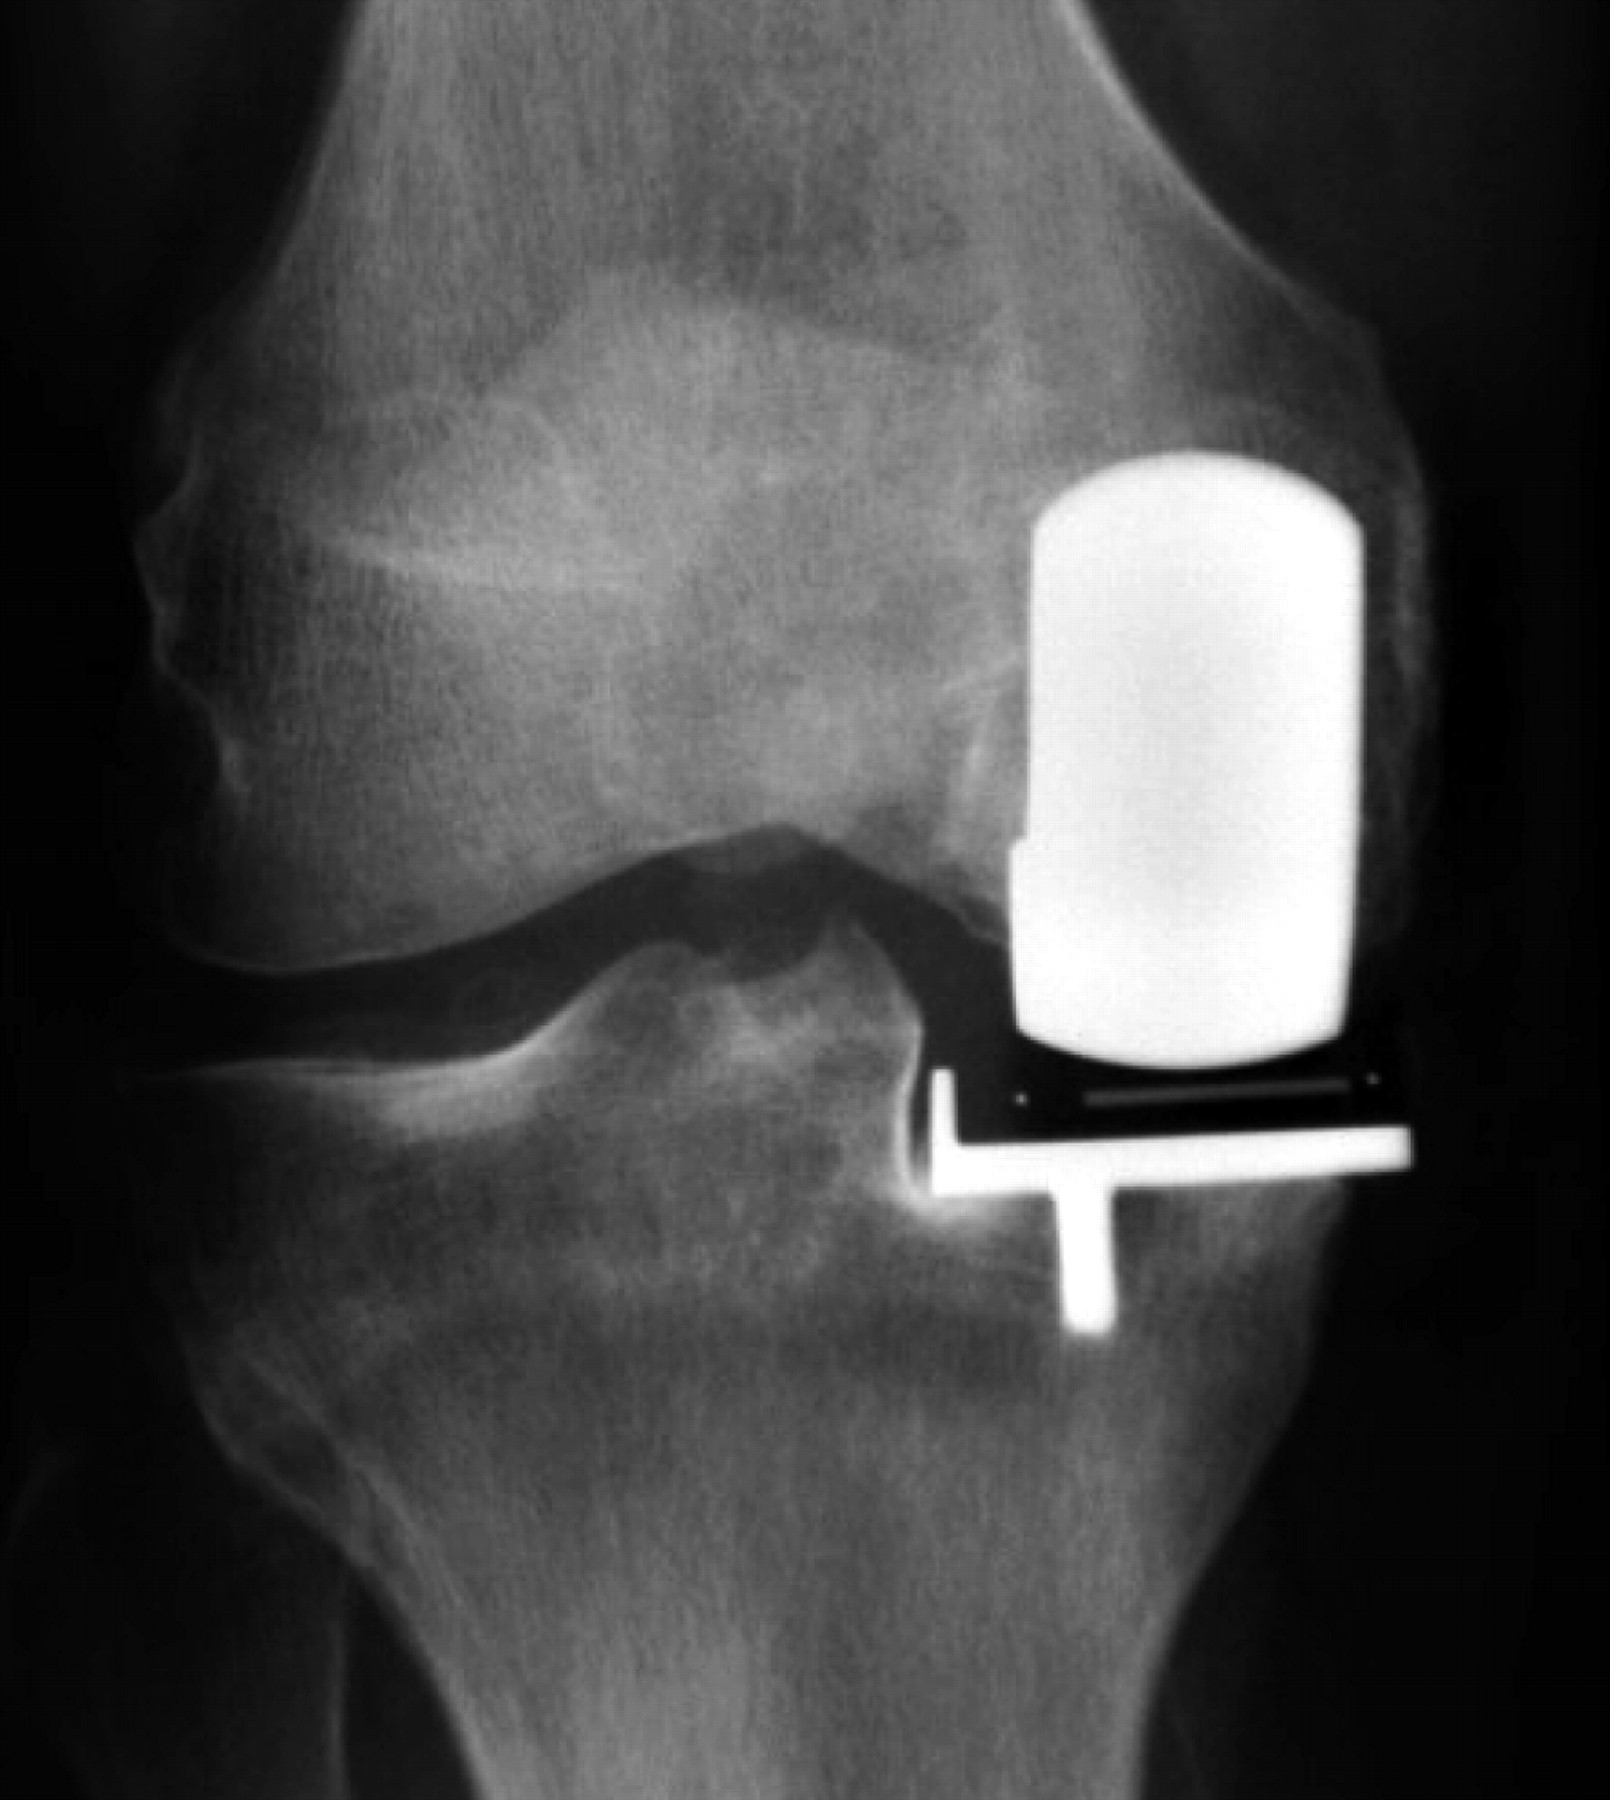

Cementless Oxford knee replacement shows reduced Radiolucent Zone We investigated the association between position change and radiolucent zone that was commonly used for diagnosing screw loosening. れ,radiolucent lineが中間群36例(46.8%),内反群14例(73.7%)であり二群間での有意差 を認めた(p<0.05)。特にgruen zone ⅲとⅴ に多く認. Radiolucent line とはステムの緩みが生じている場合にレントゲン上に出現する見え方のことです。 よくステムの成績発表などでも出てきます。 日本語の読み方は「ラジオルーセントライン」です。 このようにレントゲンでは黒く写り、主に線状に写ります。 レントゲン上でradiolucent lineが見えるという事はその場所にて 十分なbone ingrowthが起こっていない という事です。 本来固定力を発揮しなくてはいけない部分でradiolucent lineが確認出来た場合は固定力不足 と考えられます。 固定力不足により緩みがあるとステムは少なからず動いてしまいます。 Delee and charnley and gruen classified the radiolucent lines between the total hip arthroplasty and the bone seen on the ap.. Radiolucent Zone.

Assessment of radiolucent lines around the Oxford knee Radiolucent Zone れ,radiolucent lineが中間群36例(46.8%),内反群14例(73.7%)であり二群間での有意差 を認めた(p<0.05)。特にgruen zone ⅲとⅴ に多く認. The present study aimed to determine the incidence of the radiolucent zone after tka without patellar resurfacing. We investigated the association between position change and radiolucent zone that was commonly used for diagnosing screw loosening. Delee and charnley and gruen classified the radiolucent lines between the total hip arthroplasty and the bone seen on. Radiolucent Zone.

Assessment of radiolucent lines around the Oxford knee Radiolucent Zone The present study aimed to determine the incidence of the radiolucent zone after tka without patellar resurfacing. れ,radiolucent lineが中間群36例(46.8%),内反群14例(73.7%)であり二群間での有意差 を認めた(p<0.05)。特にgruen zone ⅲとⅴ に多く認. We investigated the association between position change and radiolucent zone that was commonly used for diagnosing screw loosening. Delee and charnley and gruen classified the radiolucent lines between the total hip arthroplasty and the bone seen on. Radiolucent Zone.